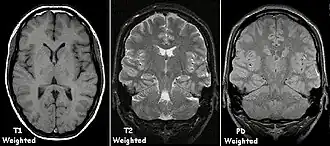

Examples of T1-weighted, T2-weighted and PD-weighted MRI scans

Each tissue returns to its equilibrium state after excitation by the independent relaxation processes of T1 (spin-lattice; that is, magnetization in the same direction as the static magnetic field) and T2 (spin-spin; transverse to the static magnetic field). To create a T1-weighted image, magnetization is allowed to recover before measuring the MR signal by changing the repetition time (TR). This image weighting is useful for assessing the cerebral cortex, identifying fatty tissue, characterizing focal liver lesions, and in general, obtaining morphological information, as well as for post-contrast imaging. To create a T2-weighted image, magnetization is allowed to decay before measuring the MR signal by changing the echo time (TE). This image weighting is useful for detecting edema and inflammation, revealing white matter lesions, and assessing zonal anatomy in the prostate and uterus.